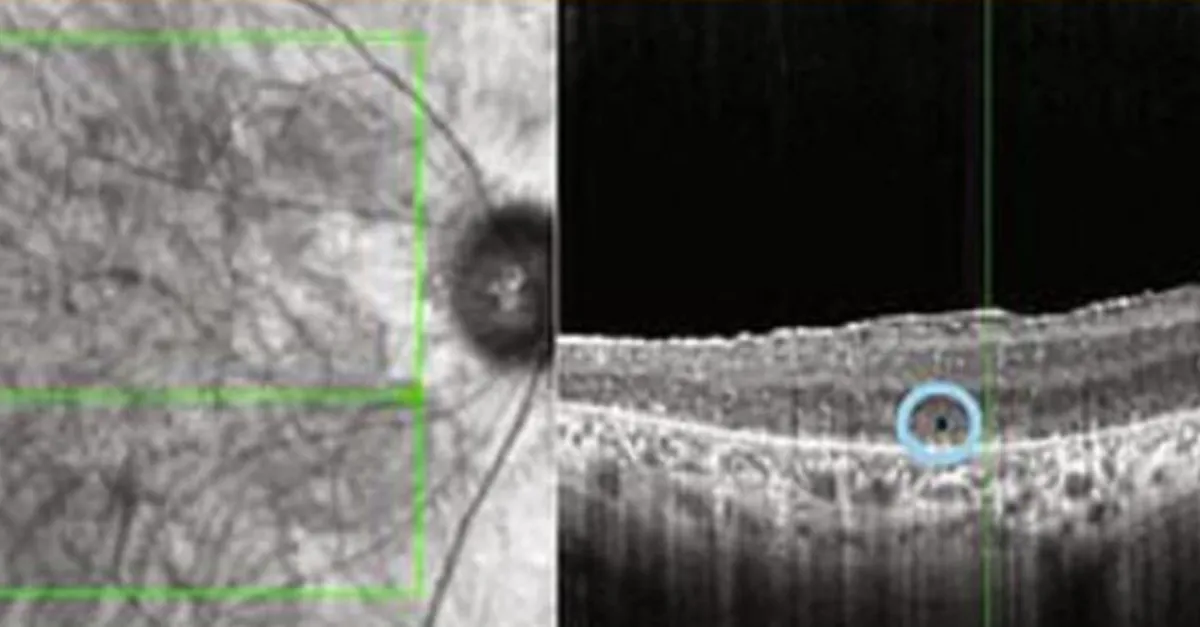

Aynı habere göre, terapi, hastanın gözlerinden birindeki hücreleri genetik olarak değiştirerek, özel bir gözlükle gönderilen ışık atımlarına tepki vermelerini sağladı.

Gözlüğün üzerindeki kamera ise gerçek dünyanın bir görüntüsünü, hastanın önündeki nesneleri tanıyabileceği kehribar renkli ışık darbelerine dönüştürdü.

Bu görüntünün siyah beyaz olduğunun altını çizen uzmanlar söz konusu yöntemin başka bir kişinin yüzünü tanımak için yeterince ayrıntılı olmadığını açıkladı.